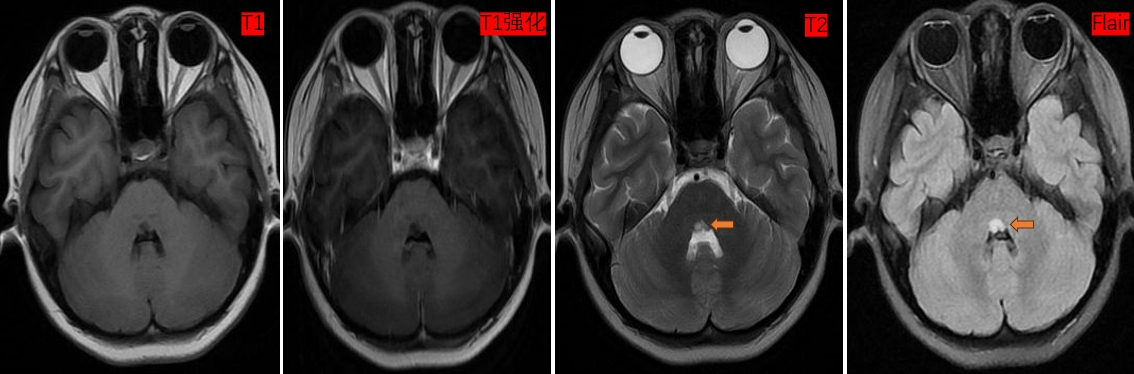

头MR(2023-11-07)提示第四脑室上方可见团块状信号影,T1程低信号、T2序列及Flair呈高信号,T1增强序列未见强化效应。